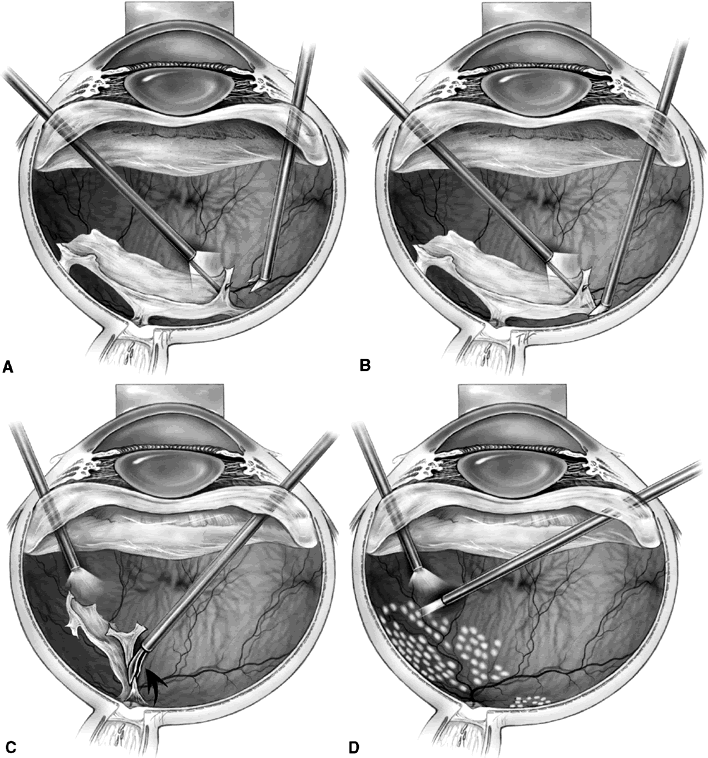

Delamination begins similarly to segmentation with the removal of the partially detached posterior vitreous surface between the vitreous base and the edge of the fibrovascular adhesions. Using bimanual techniques, from anterior to posterior, the edge of the fibrovascular membrane is reflected using either a lighted pick, lighted forceps, the light pipe, or a tissue manipulator (Fig. 2A). This allows the epicenters of adhesion between the retina and the fibrovascular membrane to be visualized. These epicenters then are amputated at the retinal surface using horizontal scissors, membrane peeling cutter scissors, or a diamond blade (see Fig. 2B). This technique is continued until all of the fibrovascular tissue has been removed up to the optic nerve head. The membrane then can be grasped with a forceps and gently avulsed (see Fig. 2C). Unlike segmentation, after membrane dissection using delamination technique, minimal or no epiretinal tissue remains on the retinal surface (see Fig. 2D). In cases with broad areas of severe vitreoretinal adhesion, a combination of delamination and segmentation may be necessary.

Fig. 2. A. A lighted pic is used to elevate and reflect the edge of epiretinal tissue so that foci of fibrovascular adhesion can be visualized. B. Horizontal scissors are used to amputate the fibrovascular adhesion at the retinal surface. C. After the epiretinal membrane has been dissected up to the optic nerve, forceps are used to grasp the membrane and gently avulse it from the optic nerve head. D. The epiretinal membrane has been completely removed, and panretinal endophotocoagulation is applied.